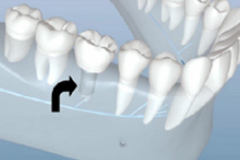

口掃取模

效果預覽

研究取模

參照評估